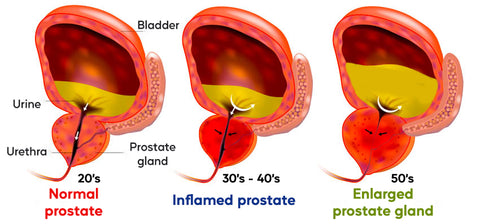

Changes in the prostate as you age

Because the prostate gland tends to grow larger with age, it may squeeze the urethra and cause problems in passing urine. Sometimes men in their 30s and 40s may begin to have these urinary symptoms and need medical attention. For others, symptoms aren't noticed until much later in life. An infection or a tumor can also make the prostate larger.